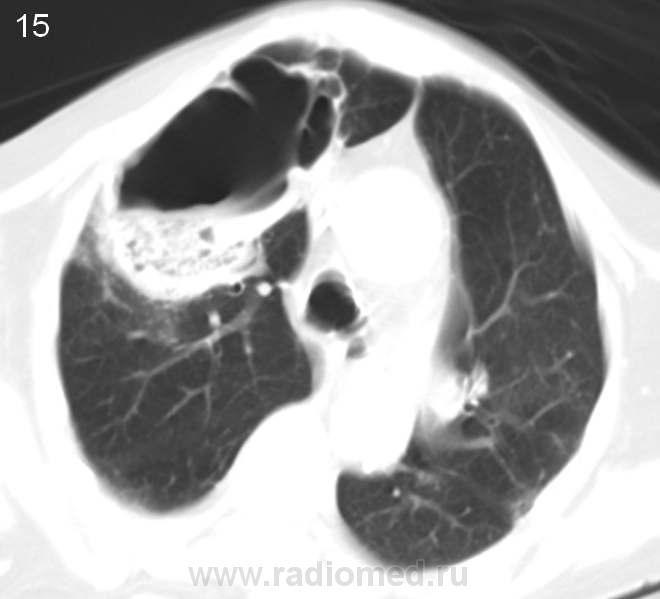

Больная 80 лет. Госпитализирована в терапевтическое отделение. Состояние тяжелое.Флюорографию не проходила много лет. Прошу высказать Ваше мнение о данной патологии. Это не игра. Диагностика заболевания. Жду. С уважением, Nikolas

Полость большая, стенки неровные, толщина различная, есть что-то вроде секвестра, но думаю- солидный компонент. На первое место выставил бы полостную форму рака, а остальное в виде вторичного наслоения. За ТЭЛА не думаю, была бы клиника, да и распад слишком большой.

Кровь и мокрота: что в анализах? Температура? Состояние тяжелое, а какова клиника, анамнез заболевания - остро, хронически? Есть ли динамика снимков? Есть ли связь с органами брюшной полости? Одни вопросы sad. Ни верхушек, ни низушек, полной картины не складывается, и без мягкотканного окна только гадать остается. Будь у меня такое исследование без ничего, написала бы полостное образование (диф.ряд от толстой кишки в грудной полости до абсцесса легкого).

1)синдром кольцевидных теней  ,неправильной формы с толстыми стенками ,наличием в некоторых горизонтального уровня ,2)уплотнения по типу матового стекла(вероятнее всего кровоизлияния) ,3)синдром круглой тени(вероятнее всего гранулема),4)синдром очаговых теней ,5)локальное субплевральное уплотнение по типу консолидации,6)мелкие сгруппированные ацинарные тени,7)субплевральные линейные тени(фиброз),8)единичный крупный л.у. параэзофагеальной группы со сниженной дкнситометрической плотностью,9)крупная параэзофагеальная грыжа,10)левая доля печени со сниженной денситометрической плотностью?(есть сомнения ввиду лишь нативного исследования ).исключить гранулематозы(туберкулез и вегенер) и грибковое поражение

Справа вокруг полости до противного чисто... ну немного паренхима поджата, что неудивительно. Полость крупная, с перегородками, с некротическими массами и жидкостью, стенки неравномерно толстые. На первом месте выставила бы полостную форму рака (либо солитарный гигантский мтс с распадом), на второе - туб.каверну (нет отсева или я не вижу, что как-то мало подходит под тбс), на третье - гигантский абсцесс (такая ареактивность, что лимфоузлы не отреагировали?...). Возможность грибов мне кажется достаточно маловероятной. Вегенера и последствия инфаркта при ТЭЛА тоже возможно, но такая крупная полость в 80 лет мне кажется для этих вариантов также маловероятной. Могу ошибаться.

- сегментарная локализация: посмотрите - деструкция занимает четко ограниченную анатомическую зону, широко прилежит к плевре (субплеврально)

- форма: клиновидная

- контуры: неровные, как бы "полицикличные" контуры деструктивной полости - очень характерный признак для больших инфарктов. Туберкулезные полости обычно имеют более правильные контуры (если конечно они не совсем старые, но при этом вокрг должен быть явно выраженный фиброзный процесс - тут этого нету)

- стенка - не толстая! При опухолях маловероятно что была бы такой толщины стенка. Причем она относительно равномерная. (на нижний отдел не смотрите - там секвестр остался от легкого а не стенка).

- характер секвестра - ячеистого характера (довольно типично выглядит). Правда и не при ТЭЛЕ выглядит подобно, но все же..

Ну и самое оснвое: в  окружающем легком явных изменений, ожидающихся при других патологических процессах не выявлено: например при такой деструкции при тбц ожидались бы очаги или выраженый фиброз, при опухоли с такой деструцкции тоже ожидали очаги, лимфоузлы, обструкцию бронхов (а они спокойно проходят в дестрктивной полости), изменения в легочной архитектонике и тд.